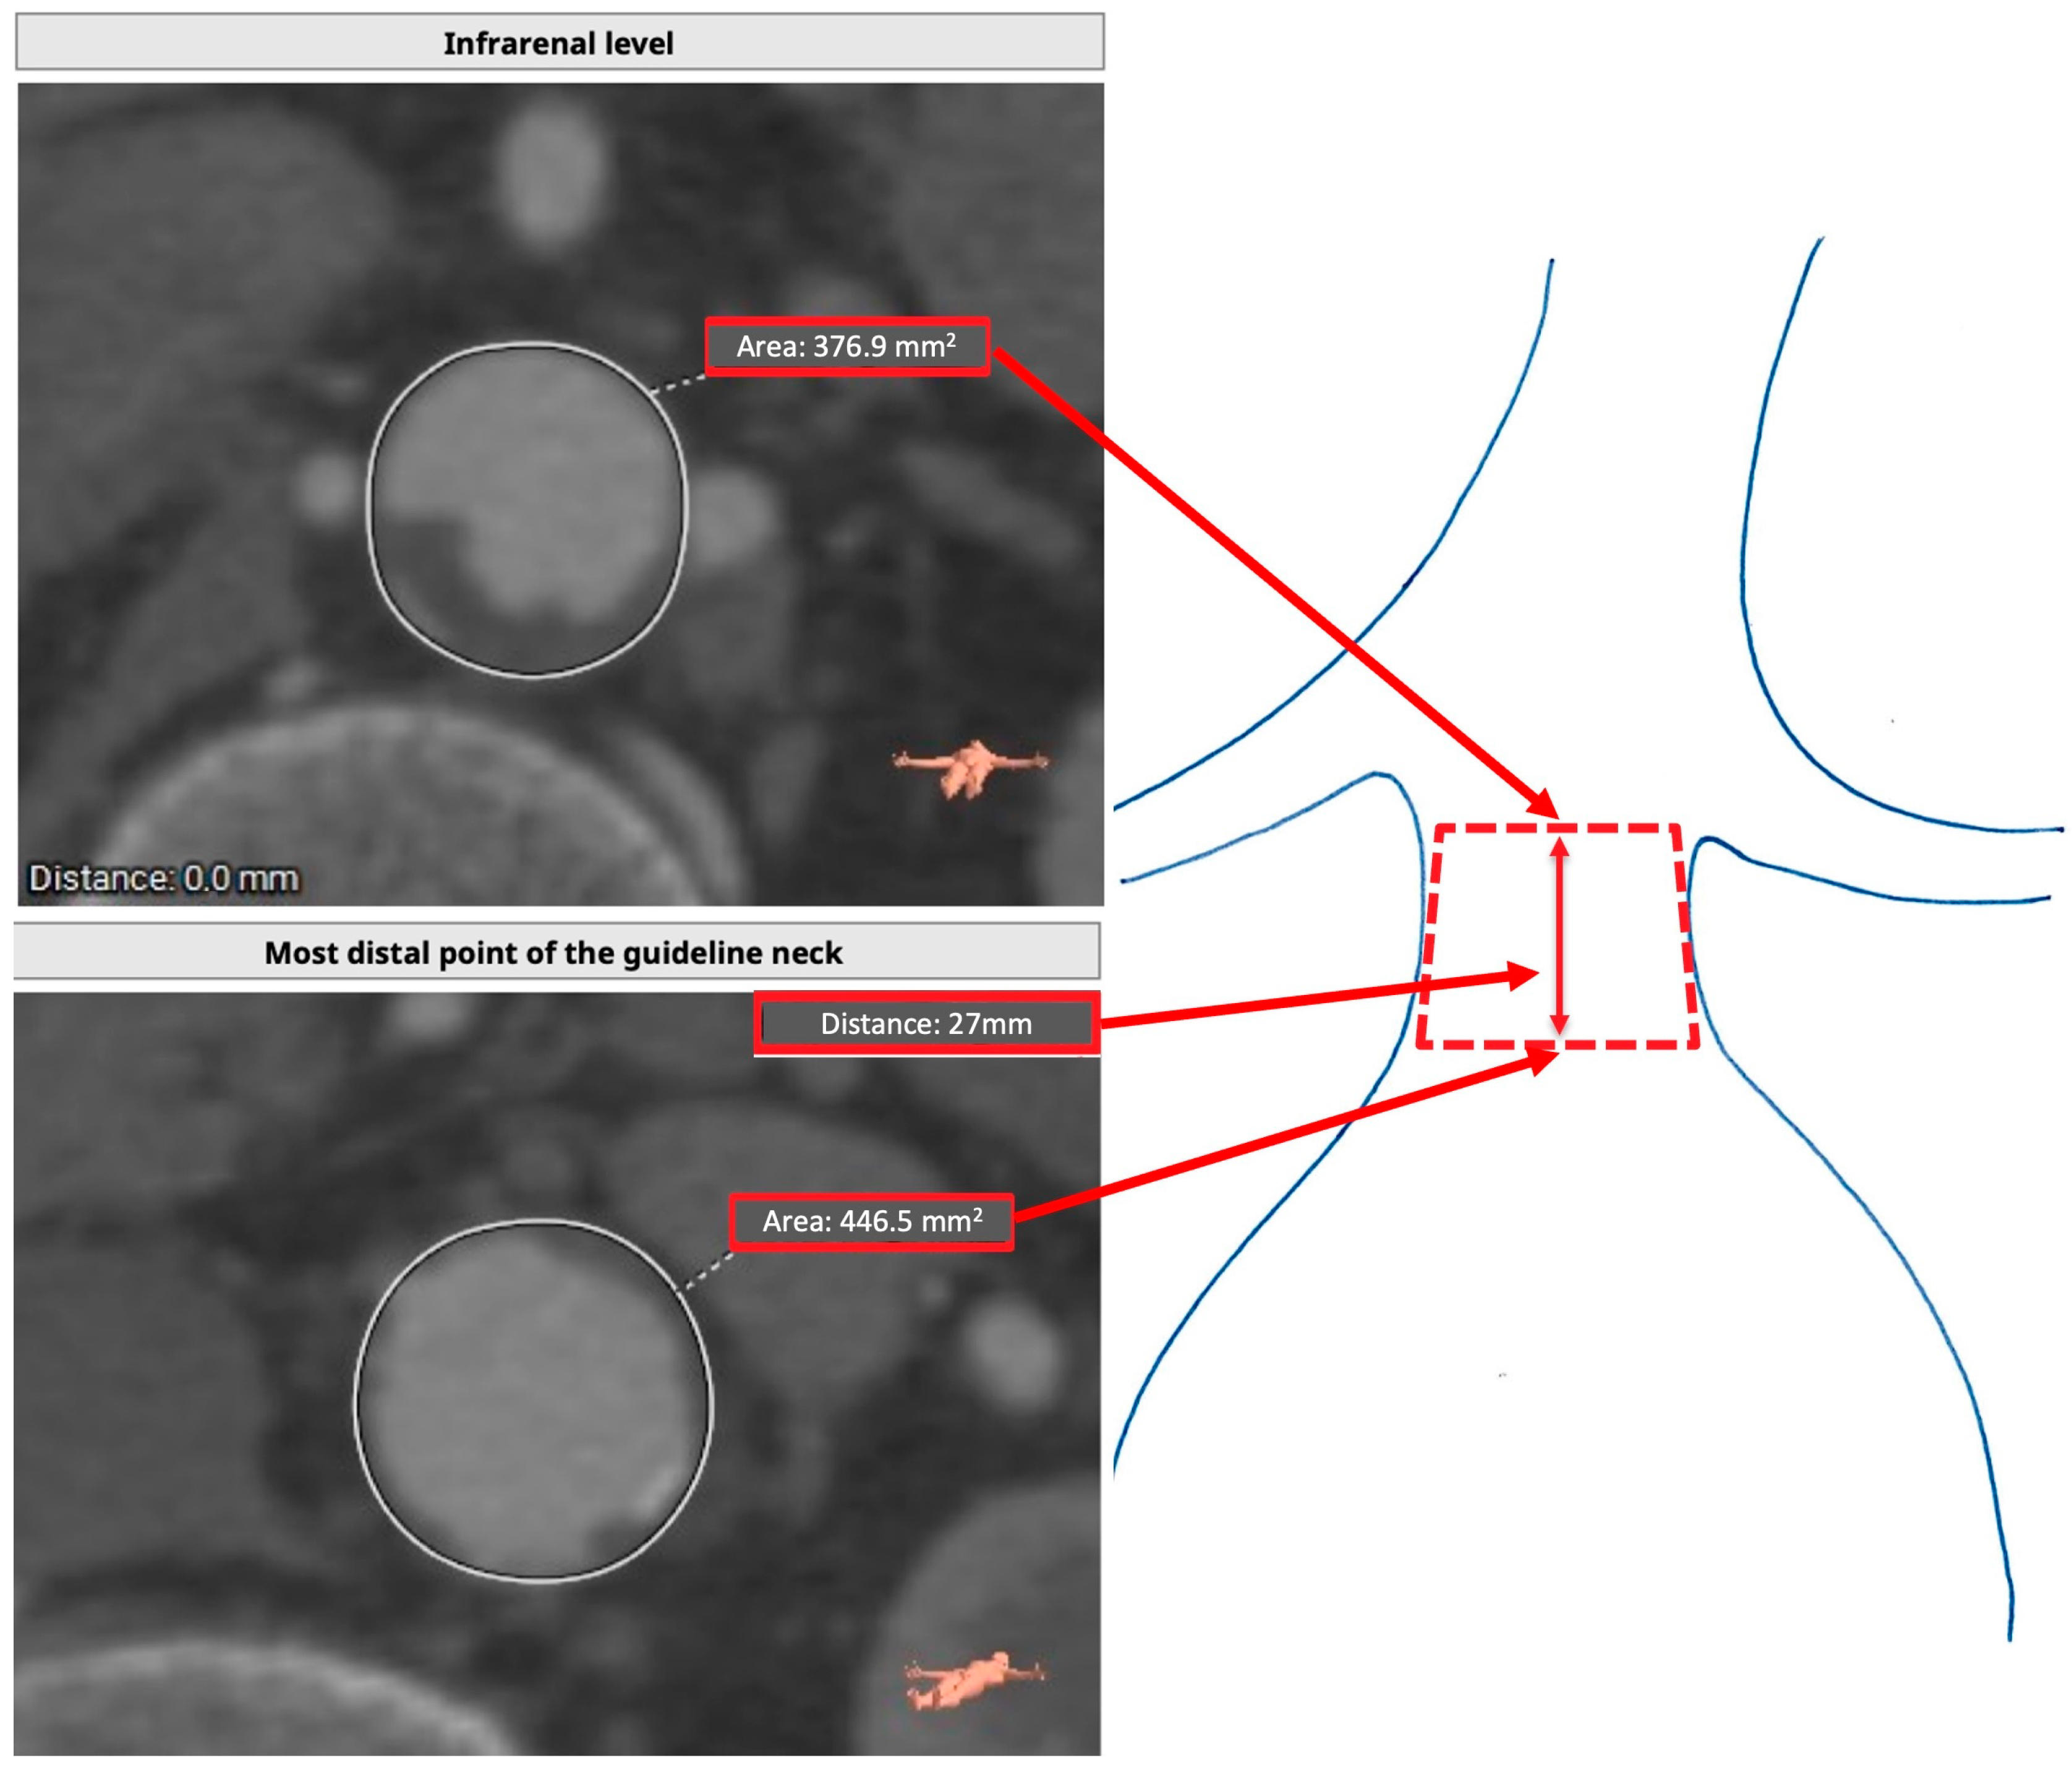

| Preoperative Assessment | Postoperative Assessment | p-Value (<0.05) | |

|---|---|---|---|

| Sealing area (mm2) | 106 (50.0–210.1) | 78 (34–155) | <0.001 * |

| Infrarenal area (mm2) | 37.8 (31.5–47.4) | 38.1 (31.5–45.9) | 0.530 |

| Proximal sealing zone length corrected for graft misplacement (mm) | 15 (7–30) | 11 (4–22) | 0.001 * |

| Most distal point of neck/stent apposition area (mm2) | 43.1 (36.1–52.8) | 40.6 (33.4–51.9) | 0.374 |

| Distance between infrarenal level and most distal point of guideline neck (mm) | 15 (7–30) | 15.5 (7–33) 15 (7–30) if type 1a splits groups | 10 (7–13) 8 (8–11) if type 1a splits groups | 0.012 * 0.029 * if type 1a splits groups |